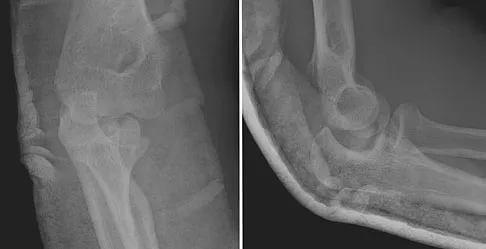

A 15-year-old boy falls from his bicycle and sustains an injury to his elbow. Prereduction radiographs are shown in Figure 12a. Closed reduction is performed without difficulty and postreduction radiographs are shown in Figure 12b. What is the next most appropriate step in treatment?

Elbow dislocations in children are rare injuries and usually result from a fall on an outstretched arm. The incidence of these injuries increases as patients age and concurrently the incidence of supracondylar humerus fractures decreases. In adolescent patients, simple elbow dislocations are treated with splint immobilization and the initiation of physical therapy once comfortable. The practitioner must be aware of structures that may get caught in the joint on reduction. These include the median nerve as well as the medial epicondyle. In this patient, the radiographs reveal a medial epicondyle fracture. Postreduction radiographs show the joint to be incongruous secondary to intra-articular displacement. At this point, the most appropriate treatment is to perform an open reduction and repair of the medial epicondyle fragment. Rasool MN: Dislocations of the elbow in children. J Bone Joint Surg Br 2004;86:1050-1058.